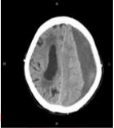

6. 女性 86 歲,近日來嗜睡,今早叫不醒,被送至急診室。家屬表示約 3 週前曾經跌倒, 頭部雖有撞到傢俱,但無明顯外傷。目前腦部電腦斷層檢查結果如下圖,病人最可能的診斷為何?(A) 腦內出血(B) 硬腦膜上血腫(C) 硬腦膜下血腫(D) 蜘蛛網膜下腔出血